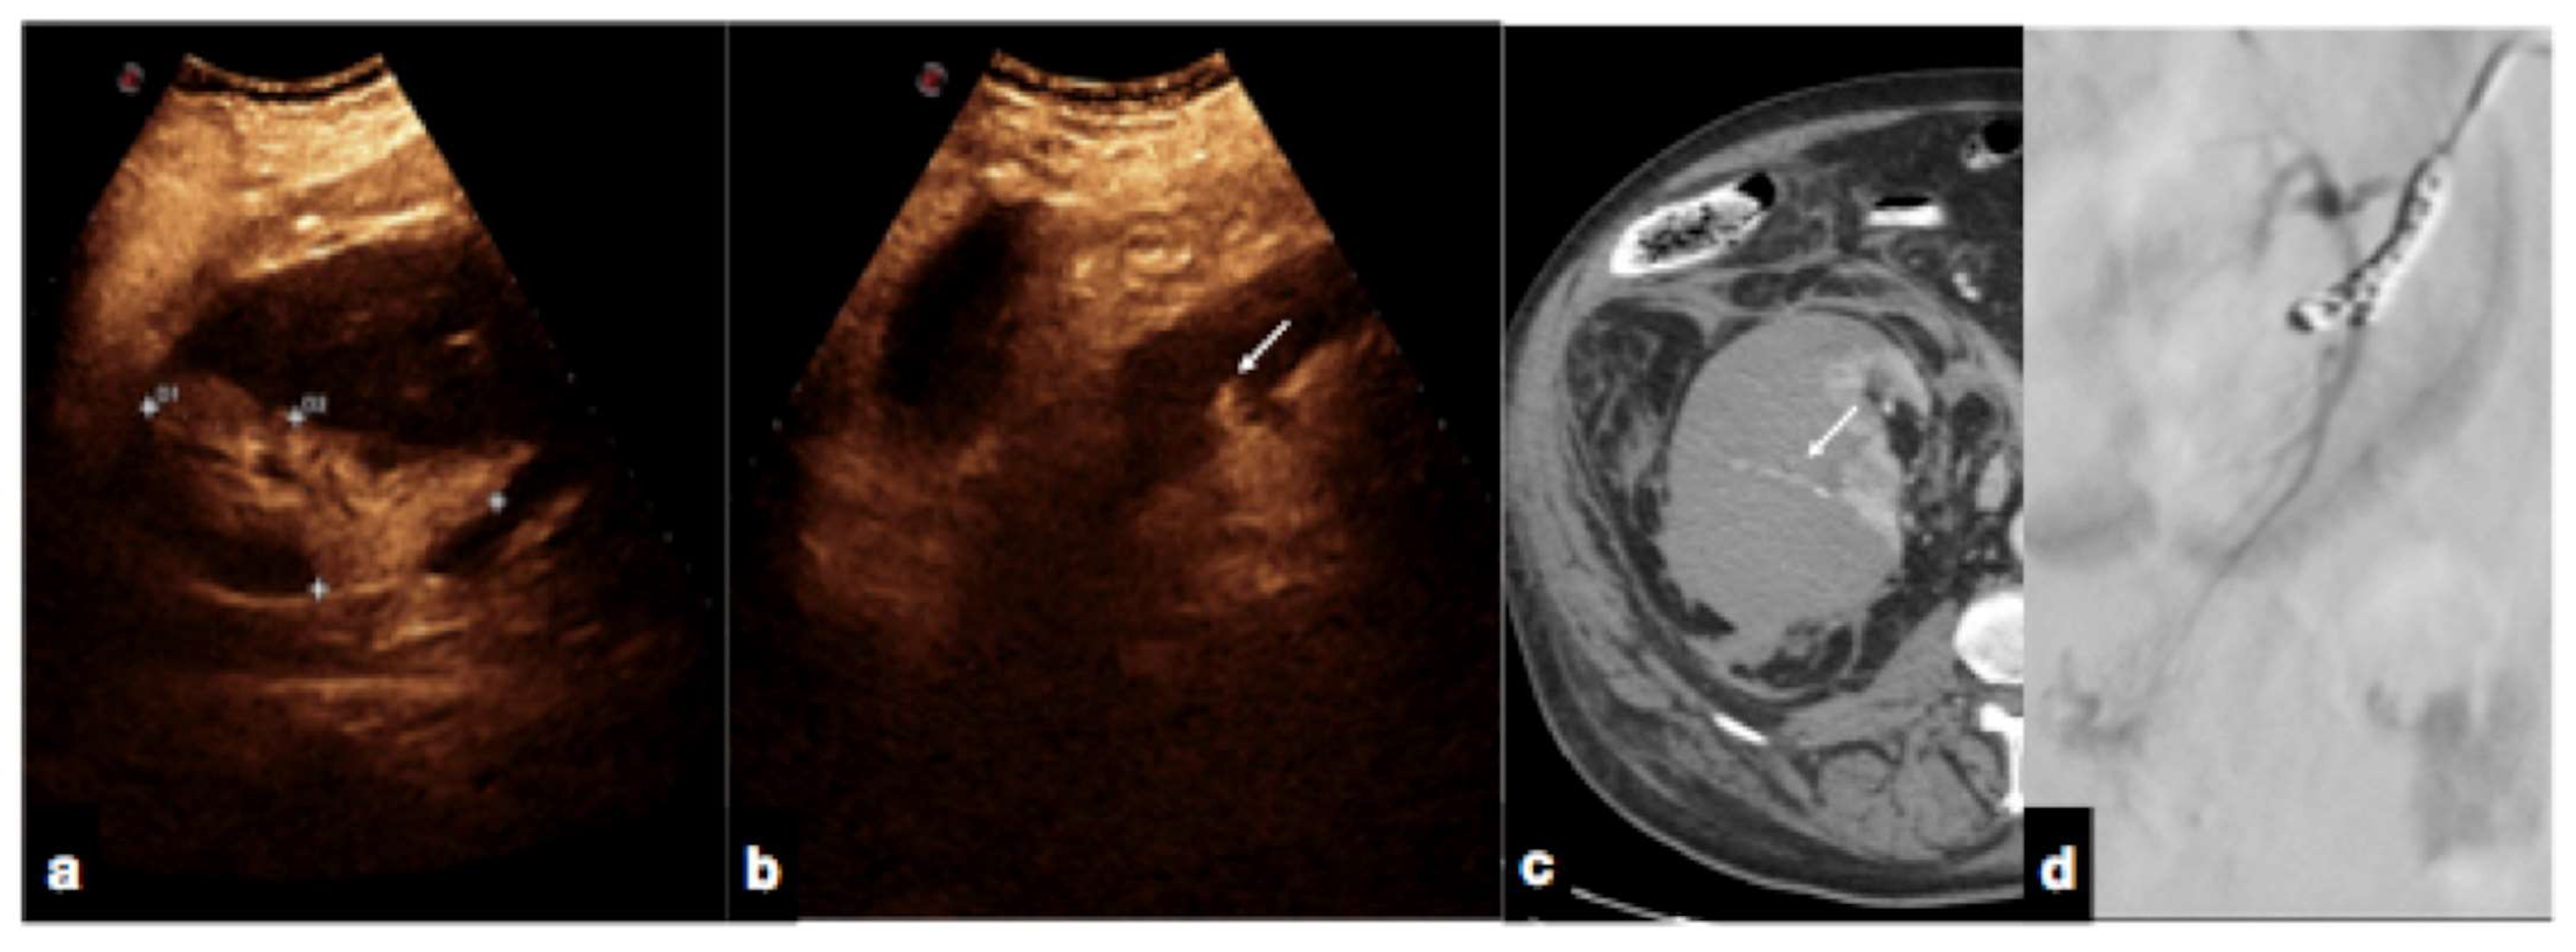

Active bleeding can be observed as micro-bubble extravasation outside blood vessels within the peritoneal or retroperitoneal space (Figure 17) [1,30].

Figure 17.

Follow-up CEUS of a 52−year-old blunt trauma patient with high-grade right kidney injury and extensive ischemia complication. Venous (a) phase CEUS examination shows multiple kidney lacerations with extensive ischemia complication and a small amount of perfused renal (caliper). At the same venous phase (b), CEUS active venous hemorrhage is well appreciated (arrow) confirmed at contrast-enhanced venous phase CT scan (c, arrow) and subsequent angiography (d).